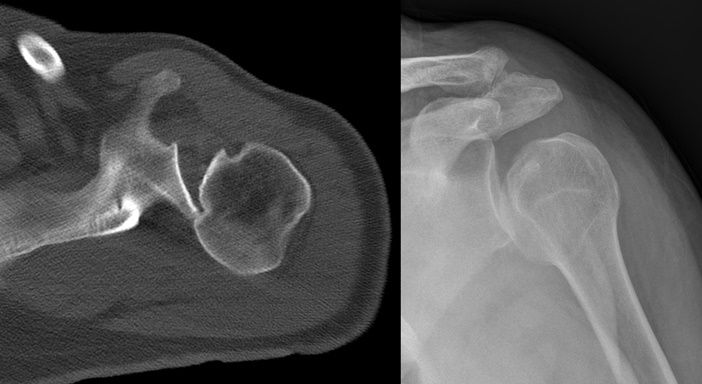

Hill Sachs lezyonu, kol kemiği (humerus) başının posterolateral kısmında kortikal çöküntü oluşması ile karakterize bir omuz yaralanmasıdır. Bu durum, genellikle anterior omuz çıkıkları sırasında meydana gelir. Özellikle humerus başı, glenoidin anteroinferior kenarına şiddetli bir şekilde çarptığında, kemikte kalıcı çöküntü oluşur.

Bu lezyonun görülme sıklığı oldukça yüksektir; tek seferlik bir omuz çıkığında %40–90 oranında rastlanırken, tekrarlayan omuz çıkıkları söz konusu olduğunda bu oran %100’e kadar çıkabilir.

Hill Sachs lezyonu, çoğunlukla bankart lezyonu ile birlikte ortaya çıkar. Bankart lezyonu, glenoidin anteroinferior kısmında oluşan bir yırtığı ifade eder ve Hill Sachs ile birlikte omuzun kronik instabilitesine yol açabilir.

Bu lezyon genellikle omuzun içe dönme hareketi sırasında daha belirgin hale gelir ve doğru şekilde teşhis edilmesi önemlidir. Bilgisayarlı tomografi (BT) veya MR görüntüleme ile kolun hareketi sırasında eklem yüzeyleri detaylı şekilde incelenebilir.